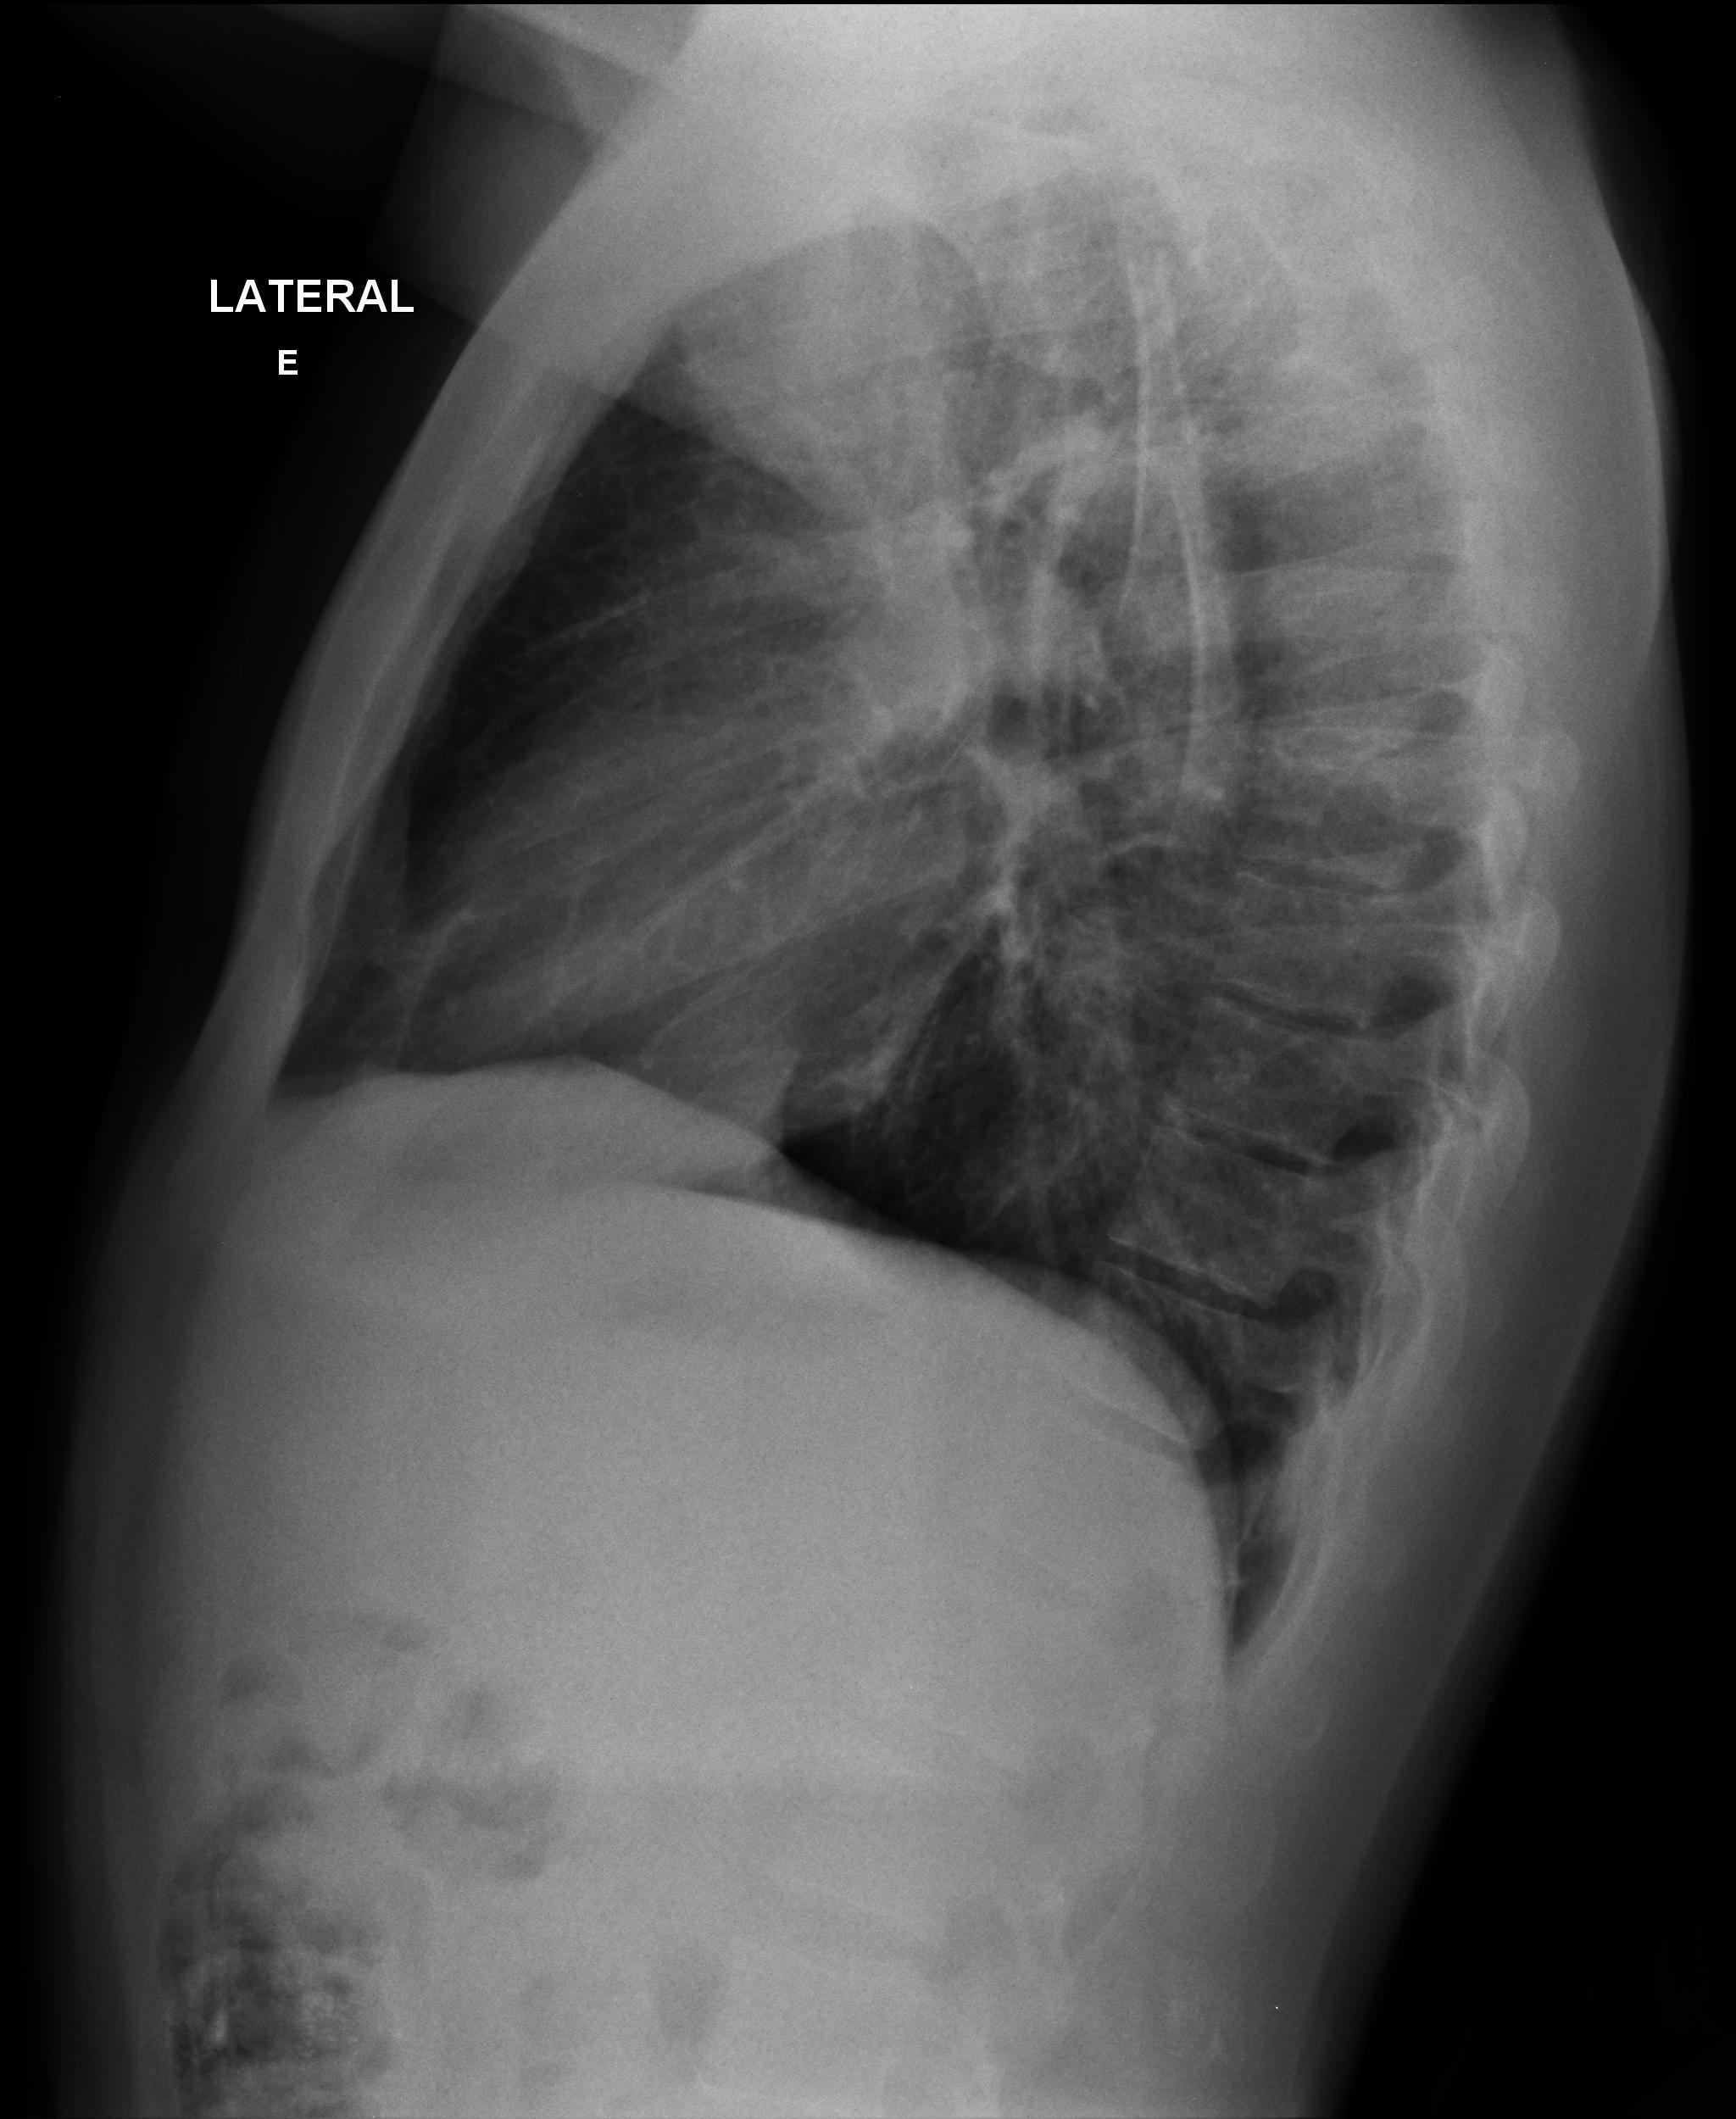

Caso Número 4/2018: “Uma sessão interativa de casos em radiologia torácica – Parte 1”

Caso relatado na Reunião de Discussão de Casos Clínicos do Hospital Universitário Prof. Polydoro Ernani de São Thiago, iniciada pelos Profs. Jorge Dias de Matos, Marisa Helena César Coral e Rosemeri Maurici da Silva, em julho de 2017. No dia 14 de junho de 2018, no auditório do HUPEST, realizou-se a apresentação e discussão do caso cujo registro é apresentado a seguir. Trata-se da discussão de onze casos em radiologia torácia, de forma interativa com a plateia, e assim ocorre também neste artigo.